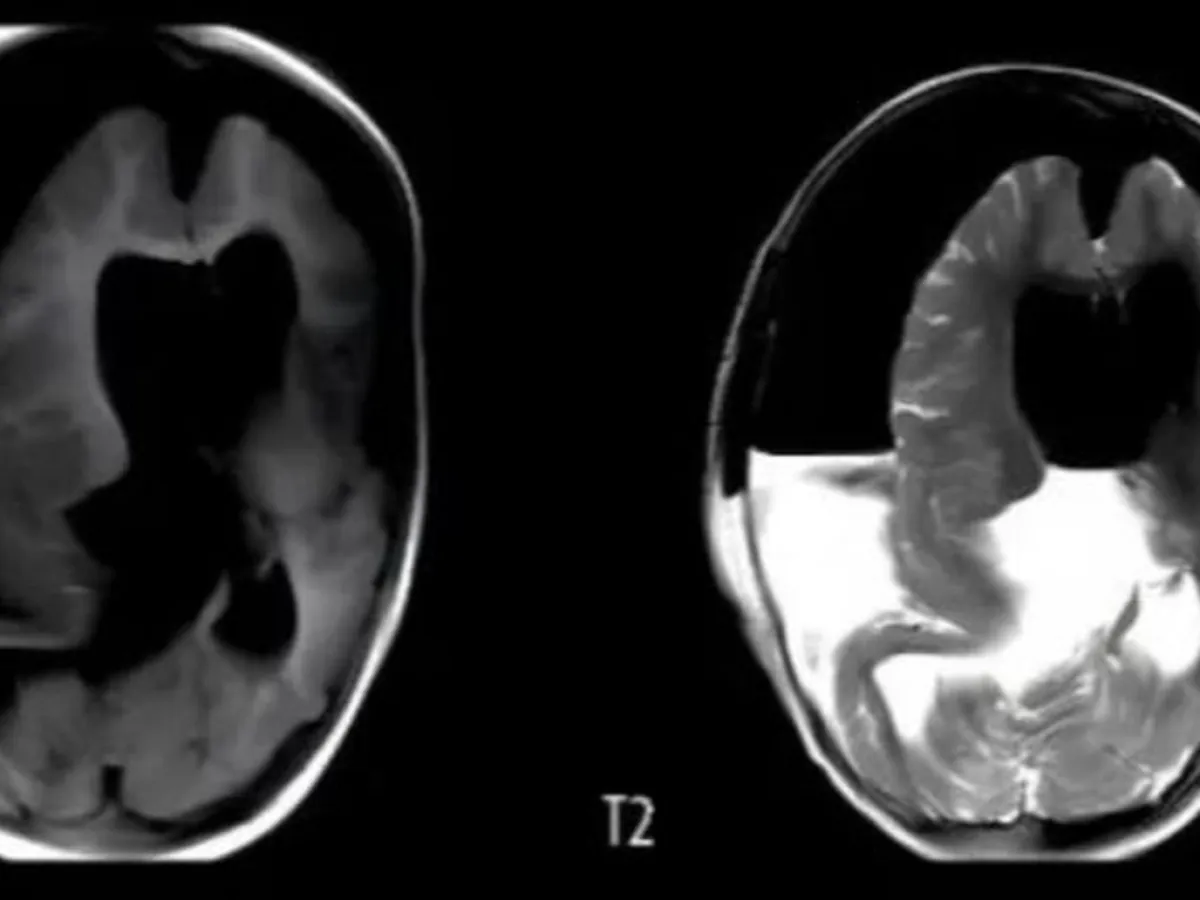

Una nena de un año tuvo que ser hospitalizada debido al gran tamaño de su cráneo y a que presentaba retrasos en sus habilidades motoras. Una vez internada le realizaron una tomografía que reveló que tenía un “tejido blando, hueso similar al de las extremidades y sombras de tejido óseo mixto en el área intracraneal”. Le realizaron una craneotomía y descubrieron que tenía un feto creciendo en su cabeza.

En el caso de esta beba, los médicos detectaron anomalías en su cráneo a las 33 semanas de gestación, durante un examen prenatal. Pero, la resonancia magnética no pudo proporcionar más información. La beba nació por cesárea a la semana 37 y los médicos notaron que su cabeza era notablemente más grande que lo normal.